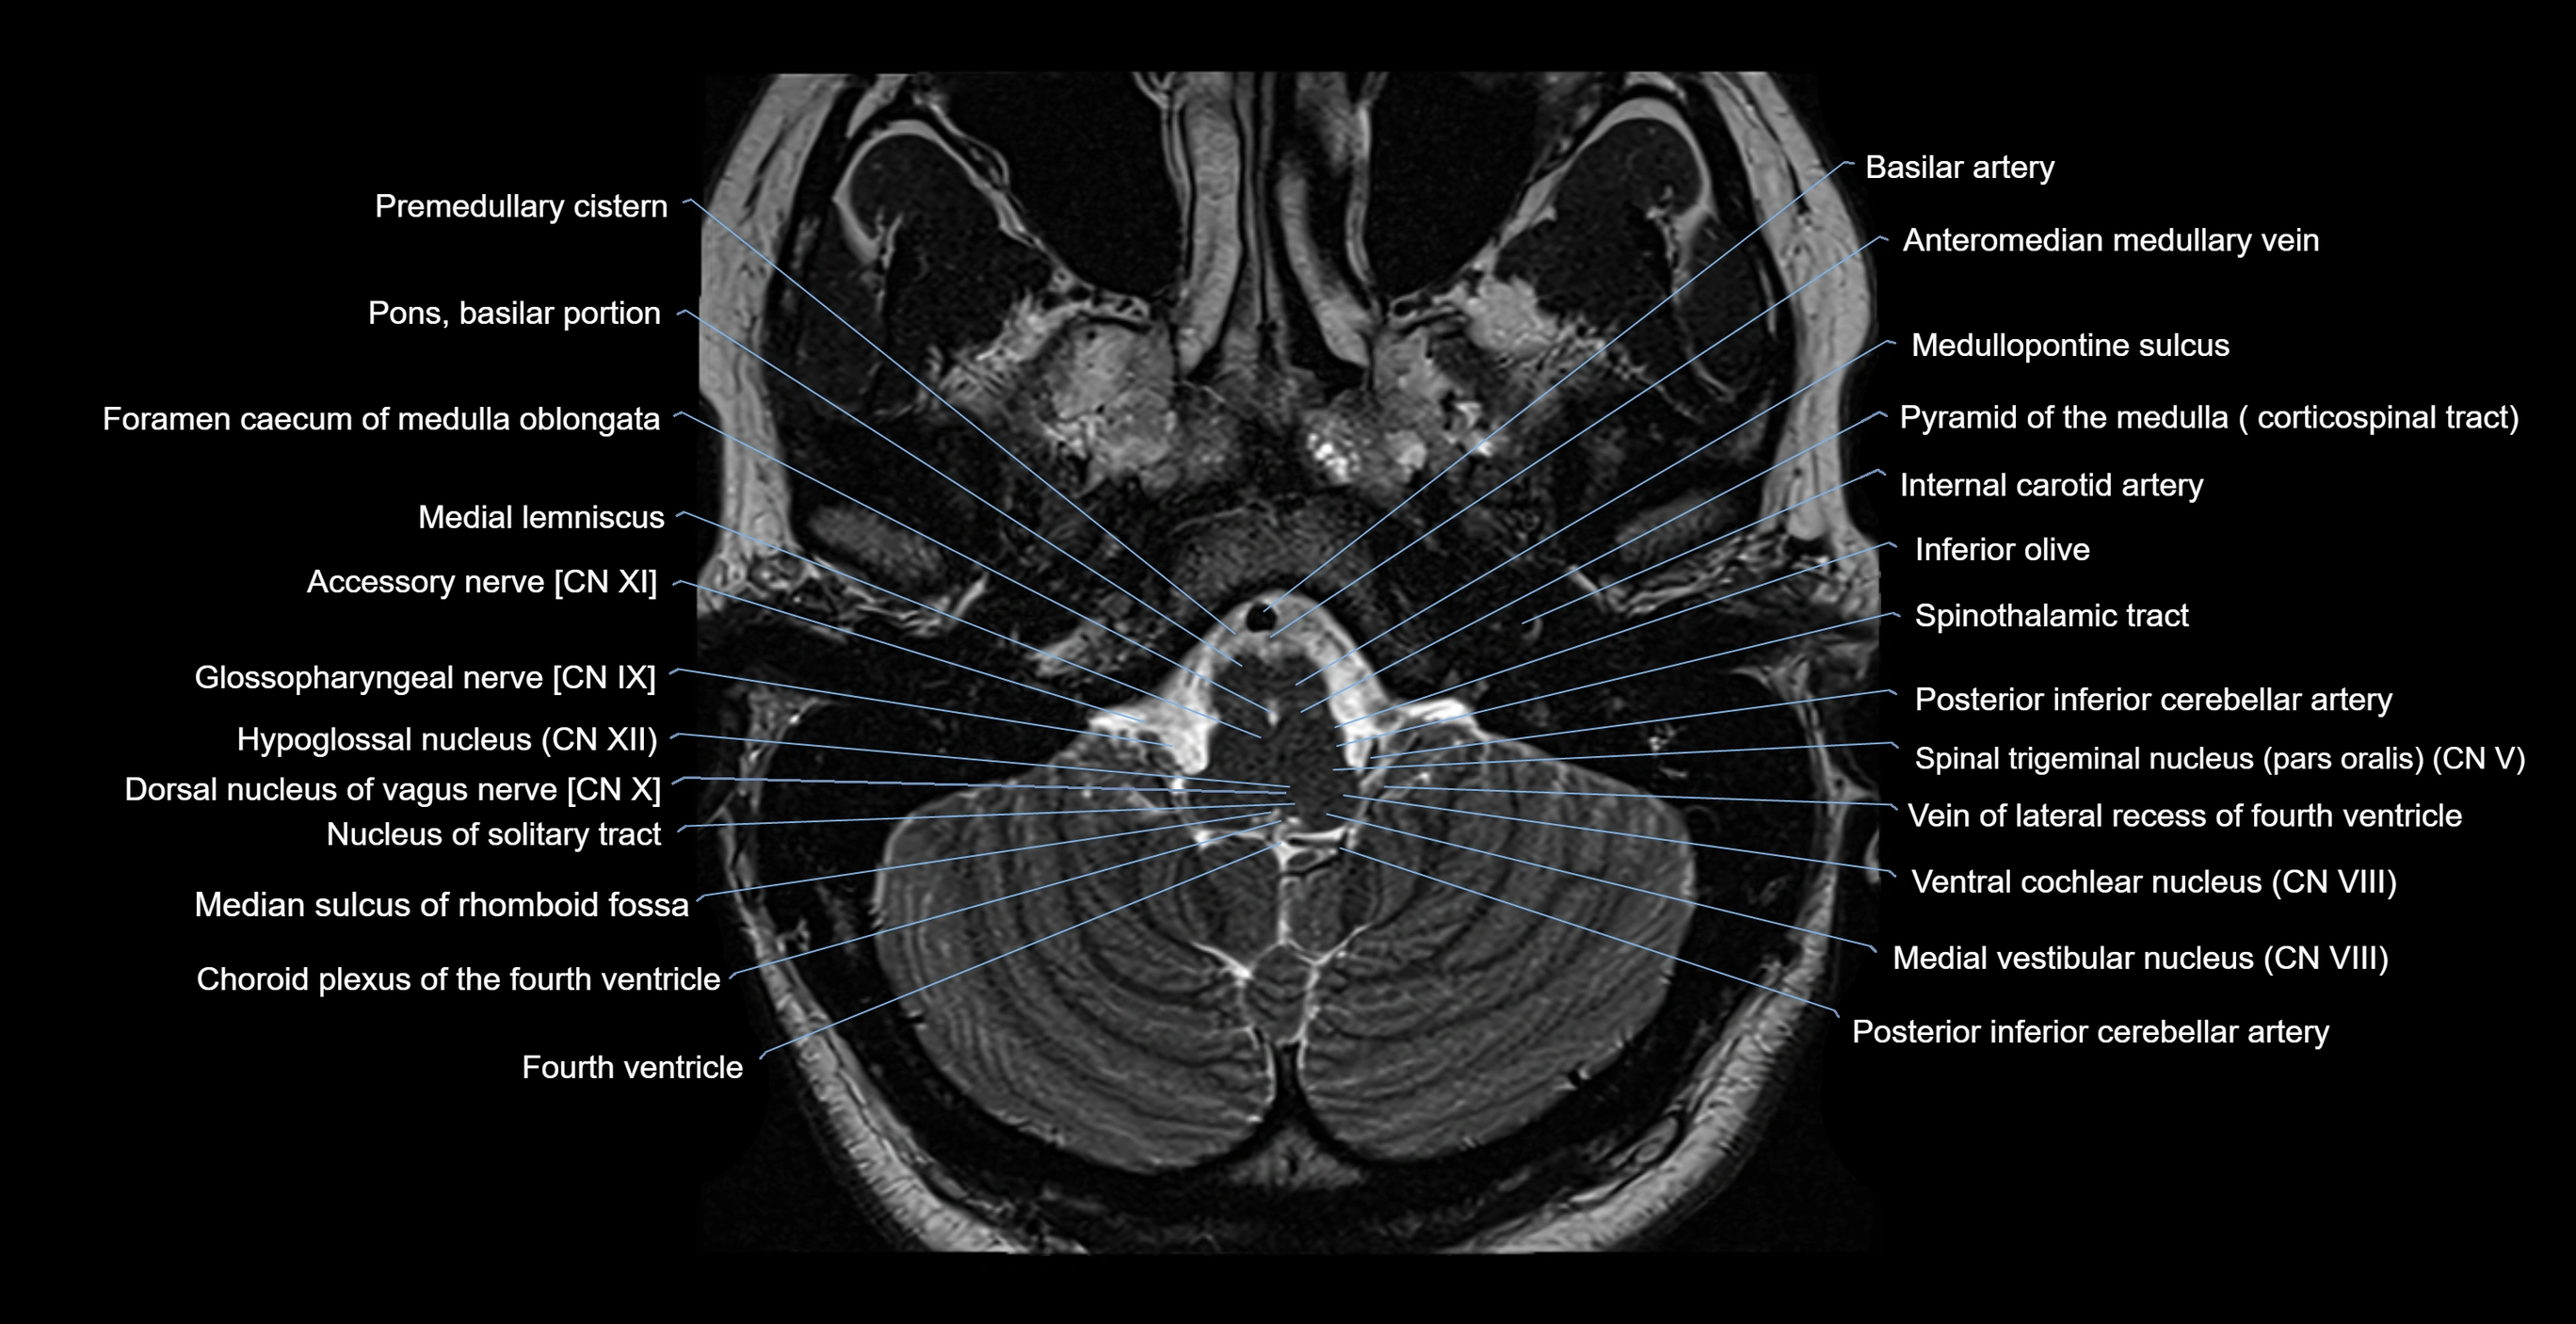

MRI images